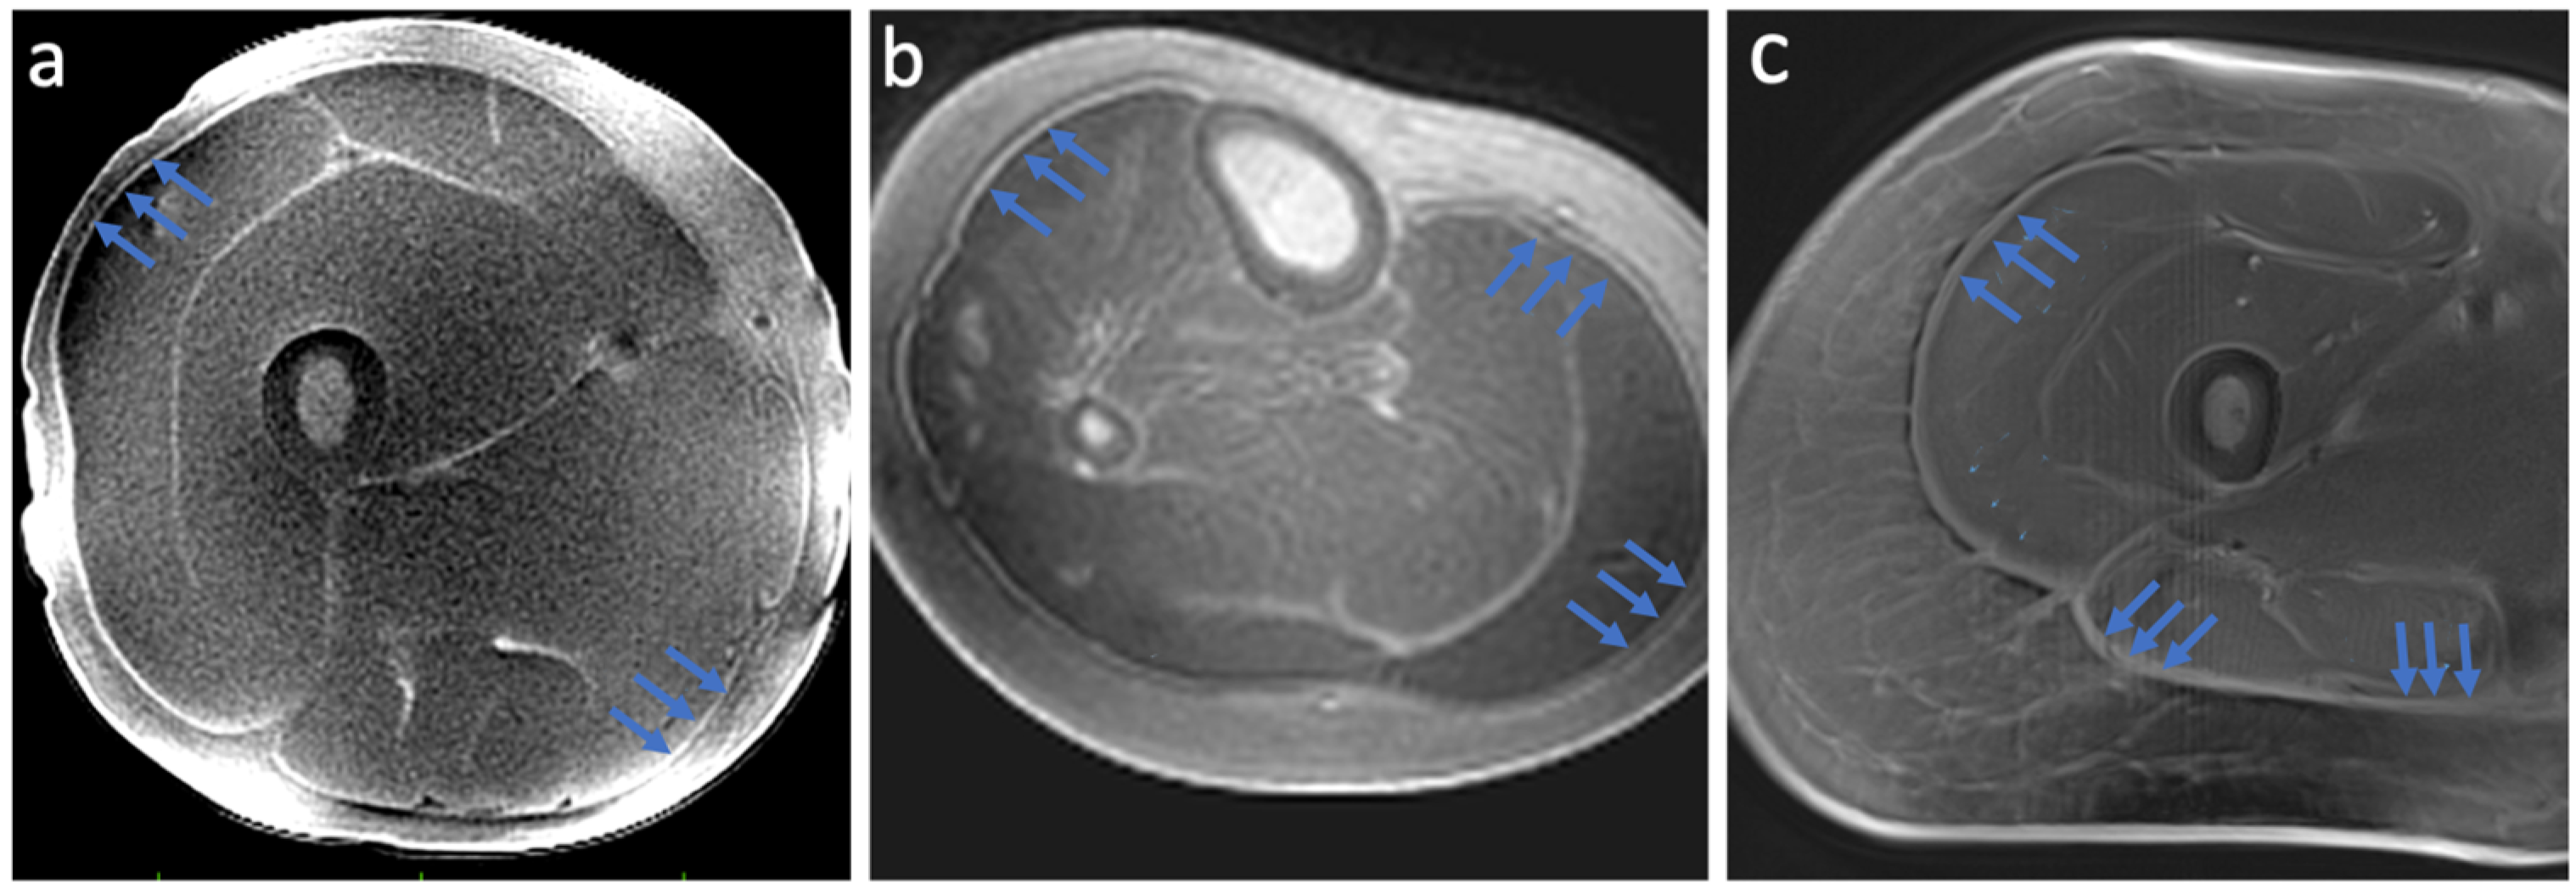

Results demonstrated high-resolution and high-contrast images of deep fascia in the lower limb (Figure 3), as well as in the aponeurosis and tendon (Figure 4). The locations of peripheral high-signal tissue we observed in our images were assessed and confirmed as deep fascia by the radiologist on our study team (GMB).

Figure 3.

Results from the dual-echo MRI sequences designed for deep fascia imaging in the lower limb. The 3D Cones sequence in the (a) upper leg and (b) lower leg. The Spiral VIBE sequence produced similar images showing deep fascia (c). Blue arrows indicate deep fascia tissue.